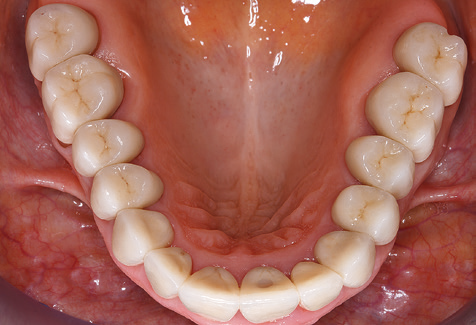

A 52-year-old patient presented in our clinic for the first time in 2004 following tooth loss in the third quadrant, expressing a desire for a new prosthetic restoration. Periodontal and radiological diagnostics revealed the need for extensive periodontological treatment. In addition, teeth 48, 28 and 27 were attributed a very poor prognosis and were subsequently extracted (Fig. 1). Following the successfully completed, systematic periodontological treatment, a fixed dental implant was inserted with the introduction of five implants in tooth regions 35, 36, 37, 46 and 47. Prosthetic treatment of the natural teeth was effected with veneered zirconium dioxide ceramic crowns; the implants were composed of two-piece, individual zirconium dioxide abutments and similarly veneered crowns made of a zirconium dioxide ceramic (Cercon base colored, Dentsply Sirona Lab). Definitive insertion of the prosthetic restoration occurred in 2005.

Due to the presence of periodontal disease, SPT was performed every three months in the first years following the insertion. The patient demonstrated a high degree of motivation and good compliance. The pocket depths recorded annually revealed a stable periodontal situation with a BOP index of below five per cent. On the basis of the stable periodontal situation and good cooperation on the patient’s part, the recall interval was extended to every six months as of the sixth year of the prosthetic function phase. Following the change in the recall interval, the respective annual documentation of the periodontal status continued to reveal a stable periodontal situation with no increase in the pocket depths and a BOP index below five per cent (Fig. 2a and b).

The ten-year check-up revealed no indications of advancing clinical attachment loss or peri-implant bone substance loss (Fig. 3).

The patient continues to visit the clinic every six months for SIT. In the following, the patient is taken as an example for demonstrating the individual working steps in a structured SPT session as it has been performed with barely any modifications over the last 12 years. Of course, some new materials and devices have been integrated into the concept over the years. This clinical case report presents the current material and device concept.

Fig. 9: The accessible implant and tooth surfaces are polished with polishing cups and suitable polishing compounds. – Fig. 10: Repeat instruction in the use of appropriate aids for oral hygiene at home should also form part of SPT. – Fig. 11a and b: Clinical situation 12 years after insertion of the prosthetic restoration. During this period, only a veneering ceramic fracture on tooth 47 and the requirement for endodontic treatment of tooth 12 were observed. All restorations are still functioning as intended.

Standardised and regular risk-adapted care in the scope of SPT is the key to treatment success for the clinical long-term success in periodontically compromised patients. This is particularly true for patients fitted with implants following successfully completed periodontal treatment (Fig. 11a and b).